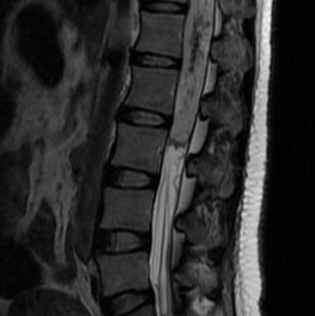

问: 什么是脊髓肿瘤 ?MRI核磁影像如何解读瘤种? 答:脊髓肿瘤是位于椎管(神经通道)中的神经和神经周组织肿瘤。根据肿瘤与脊髓和硬脑膜(包裹神经的膜)之间的位置关系...